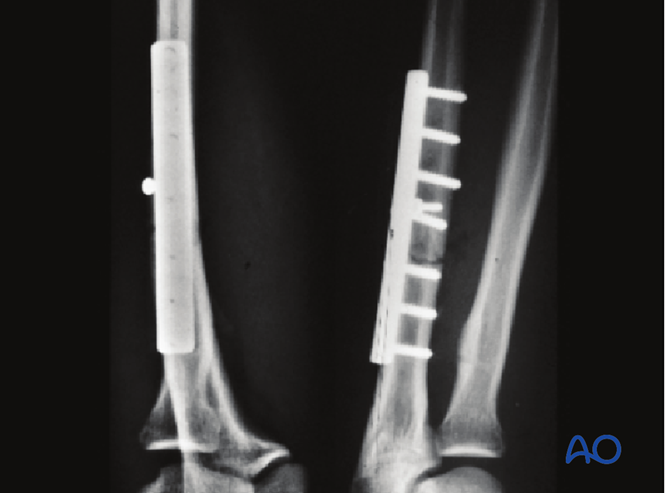

采用桥接固定联合复位钢板治疗该复杂孟氏骨折。

遗憾的是,骨折部位存在轻微间隙。如果在固定完成后移除小钢板,愈合可能会更快(见下文)。

4周时骨折仍可见,但肘关节复位良好。

术后